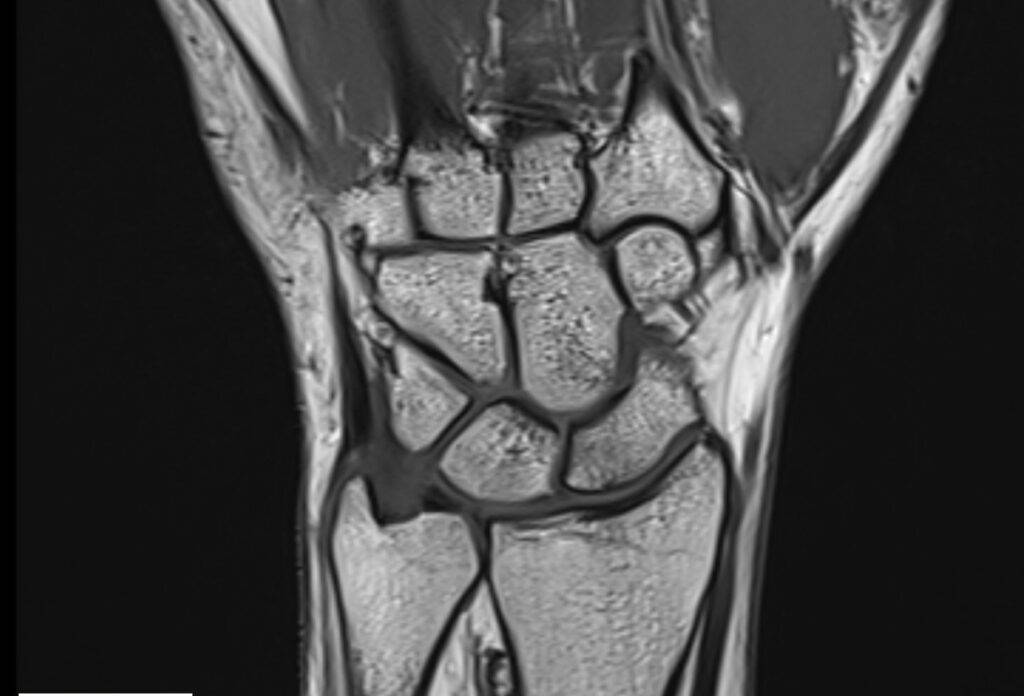

Was sieht man bei einer MRT der Hand?

Eine MRT der Hand liefert detaillierte Bilder aller vorhandenen Strukturen, darunter Knochen, Knorpel, Muskeln, Sehnen, Bänder und Nerven. Eine Hand MRT ermöglicht das Erkennen von Entzündungen, Schwellungen, Flüssigkeitsansammlungen, Rissen und anderen strukturellen Veränderungen und ermöglicht durch hochwertige Bildauflösung eine präzise Diagnose.

MRT Hand Bilder